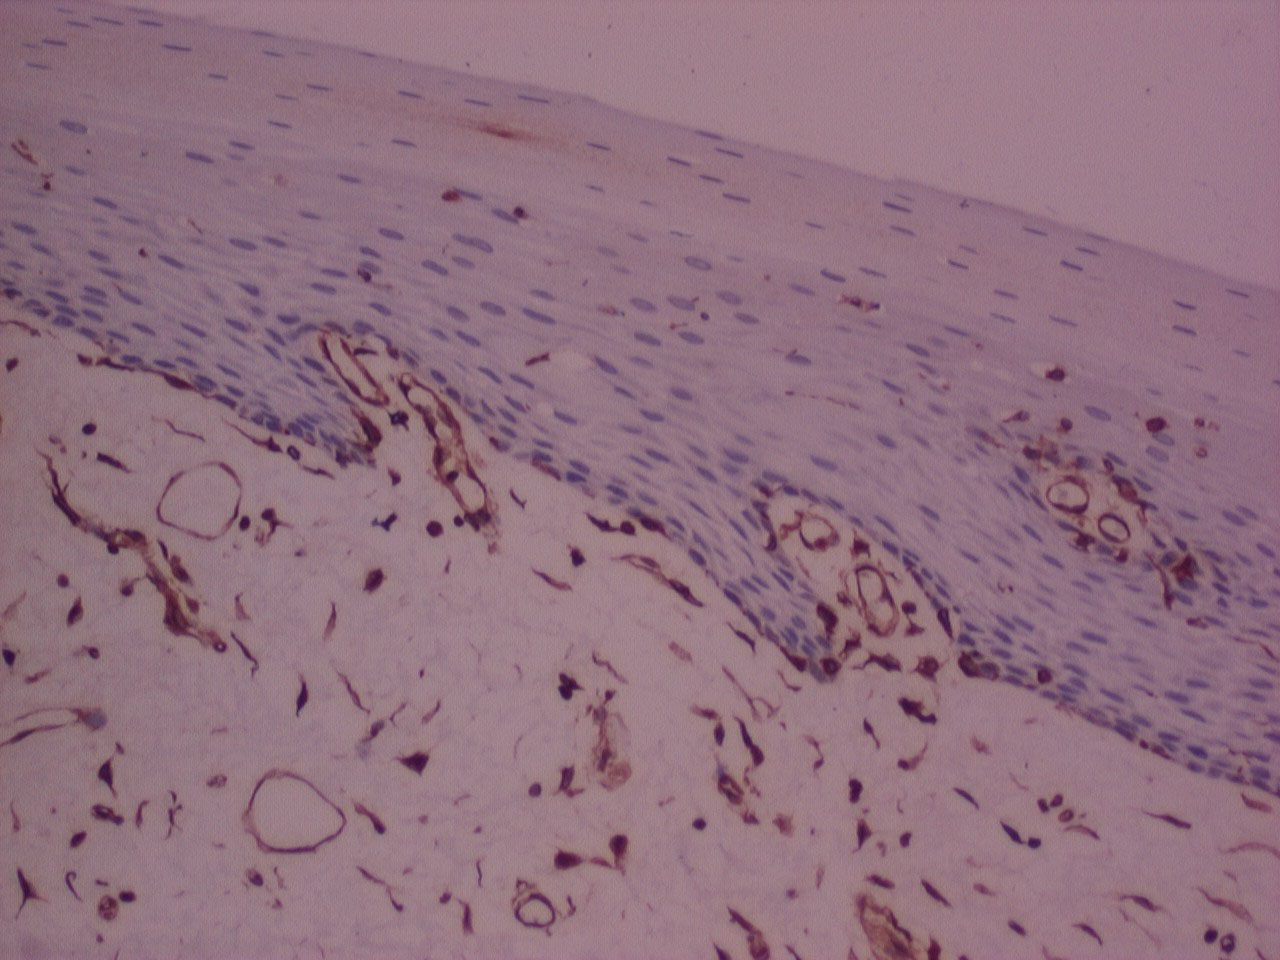

The majority of the samples processed with n-Heptane showed weak to moderate IHC staining for cytokeratin and vimentin (Figure 5, Figure 6, Figure 7, Figure 8 and Figure 9) with none of the sections devoid of staining.

Figure 7: IHC stained photomicrograph of section showing vimentin positivity, processed with n-Heptane, 10x. View Figure 7